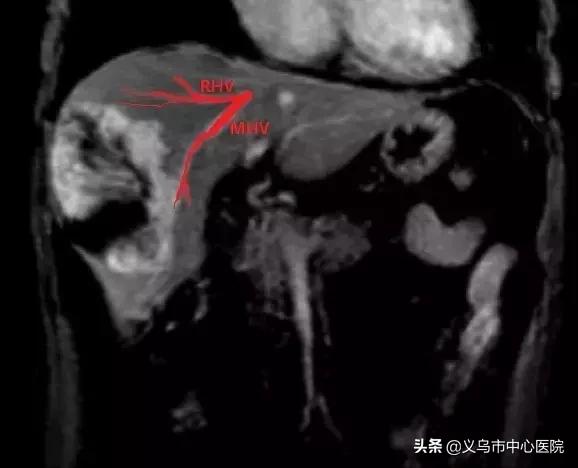

▲ MHV中肝静脉、RHV右肝静脉、肿瘤位于夹角处

由于血管瘤瘤体巨大,已经压迫了肝静脉、门静脉等肝内重要血管通道,为了最大程度地保留正常肝组织以及肝内受压迫的重要血管,同时最大程度减少术中出血量,手术必须以最快速度完成。